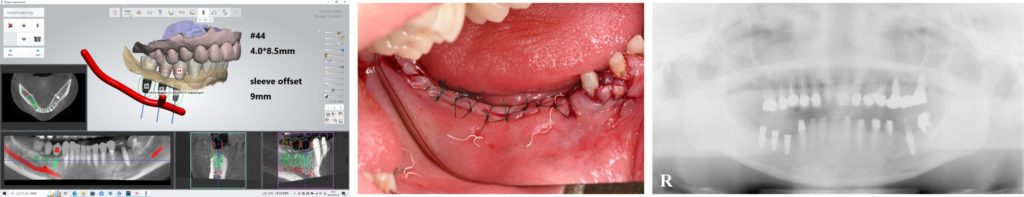

| 治療方法 | 当初は他院でインプラトができたいと言われた部分(右下)の骨造成処置後インプラト埋入手術を行なった。元々全てセラミックが入っていたが、全体的なバランス(咬合平面、咬合高径)、や歯の色に改善の余地があったため、患者との話し合いの上、可撤性のマウスピースでのトライ→接着性のトライ→セラミックへの置き換えを行なった(デジタルにて)。CADIAXにて術前、術中での顎運動の評価も行なった。 |